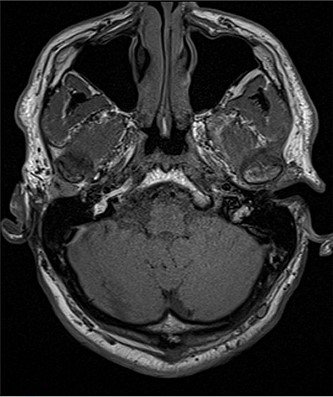

A 56- year old male was presented in the Outpatient Department of Otolaryngology Clinic with main complaint of complete aural atresia of the right ear. The clinical examination revealed that there was no external auditory canal in the right ear (Fig. 1) and hearing loss was altered (Fig. 2). There was no symptomatology in the left ear and the anatomic structures were completely normal. Blood test was normal, and there were no other medical issues from the personal history. The computed tomography (CT) scan and mainly the magnetic resonance imaging (MRI) of the temporal bone revealed no mastoid air cells and no external auditory canal and auricle (Figs 3 and 4). There was a normal anatomy of the internal auditory canal on both sides. Left side of the external auditory canal was normal. Diagnosis of this anatomical malformation was compatible with congenital atresia of the external auditory canal on the right temporal region. The patient decided to proceed to surgery many years after the first diagnosis. Some weeks ago, canalplasty and tympanoplasty were performed by our surgery team. During surgery, a graft has been obtained in order to formate the covering of the new canal. The incision was made behind the ear at the level of temporal bone, and the graft needed is removed from the temporal fascia and inserted as covering of the new canal. The aim is to create a new anatomic pathway resembling a normal external acoustic canal by drilling the atretic bone and removing the present tissue (Figs 5 and 6).